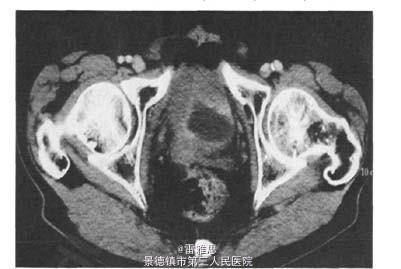

6、术后给予多西紫杉醇+草酸铂(DO方案)化疗,术后血尿明显好转,两周期化疗后,复查胸腹部cT示:膀胱壁广泛增厚,突入膀胱腔形成充盈缺损,膀胱容积显著减小,腹腔积液,右侧输尿管中上段扩张.之后调整化疗方案并行腹腔穿刺置管引流血性腹水,腹水中找到癌细胞。行腹腔灌注化疗,化疗反应明显,与家属沟通后,患者及其家属要求终止化疗。 7、印戒细胞癌为黏液性腺癌,多发于胃肠道,原发性膀胱印戒细胞癌发病较少,呈浸润性生长,常 常广泛浸润周围软组织,病程进展快,预后差,复发率高,病死率高,仅靠手术切除不可能治愈。